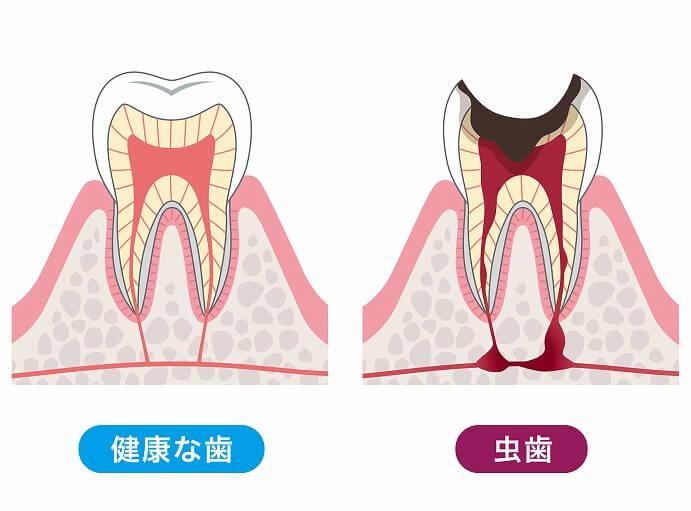

むし歯治療では歯を削ることもありますが、歯は一度削り傷ついてしまったらもう二度と元に戻ることはありません。詰め物や被せ物を使った歯科治療を行うと歯が戻ってきたように感じるかもしれませんが、残念ながら健康な歯に戻った訳ではないのです。

むし歯治療では歯を削ることもありますが、歯は一度削り傷ついてしまったらもう二度と元に戻ることはありません。詰め物や被せ物を使った歯科治療を行うと歯が戻ってきたように感じるかもしれませんが、残念ながら健康な歯に戻った訳ではないのです。

また、むし歯治療を行っても今までと同じケア方法ではまたむし歯が再発してしまう可能性も高くなります。むし歯が出来たら治療することは可能ですが、それを何度も繰り返していくとそのうちに自分の健康な歯はどんどん無くなり、更に残った歯も弱くなっていってしまうということに。